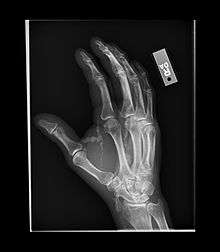

Tumoral calcinosis

Tumoral calcinosis is a rare condition in which there is calcium deposition in the soft tissue in periarticular location i.e. around joints.[1] The accumulations are outside the joint capsule. They are frequently seen in patients undergoing renal dialysis. It is also considered by some to have a hereditary predisposition. The name indicates calcinosis (calcium deposition) which resembles tumor (like a new growth). They are not true neoplasms - they don't have dividing cells. They are just deposition of inorganic calcium with serum exudate. Children and adolescents (6 to 25 years) are the most commonly affected. The symptom that the accumulations cause is not pain but swelling around joints. They have propensity to enlarge progressively and ulcerate the overlying skin and extrude. They are most common around shoulders, hips and elbows. Laboratory evaluation reveal normal serum calcium levels and hyperphosphatemia. Rarely ALP (alkaline phosphatase - an enzyme active at sites of bone formation) may be elevated. Treatment is normalization of serum phosphate levels and resection of lesion. Surgical removal should be complete and if part of it is left, there is inevitable recurrence. Cutting through the excised calcium deposition reveals semifluid calcium suspension in albumin encapsulated by fibrous tissue.